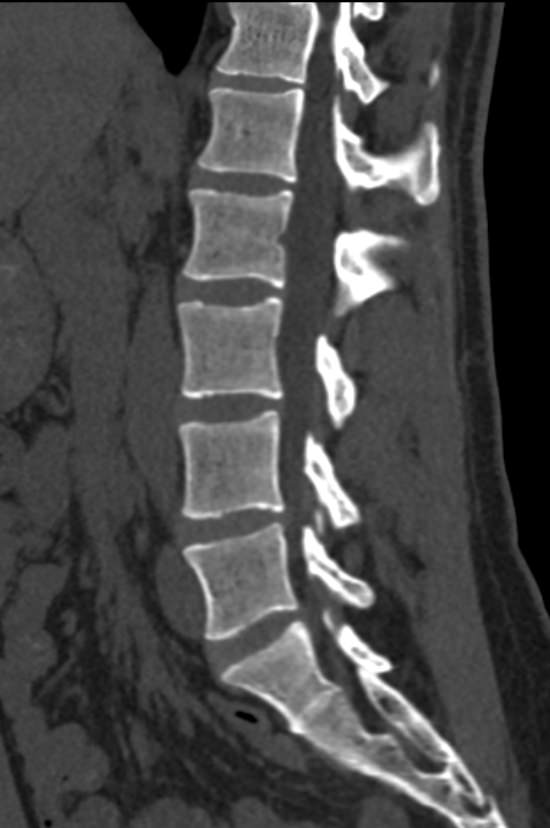

Для диагностики даже незначительных патологических изменений в различных отделах позвоночника, особенно в случае распространенного поражения, применяется один из современных наиболее информативных методов обследования – мультиспиральная компьютерная томография всего позвоночника. Методика основана на использовании проникающей способности рентгеновских лучей через органы и ткани человека и позволяет получить подробное изображение всех структур позвоночного столба. В комплексное обследование входит исследование шейного, грудного, пояснично-крестцового отделов позвоночника и копчика.

В медицинских центрах «Доступная медицина» сканирование всего позвоночника выполняется на новейших мультиспиральных компьютерных томографах последнего поколения TOSHIBA AQUILION в различных модификациях. Особенностью данных аппаратов является их способность проводить от 64 до 128 тончайших срезов одномоментно с минимальной толщиной от 0,5 мм.

Увеличенное количество высокочувствительных детекторов, которыми оснащены томографы, позволяет получать послойные снимки высокого качества с большой скоростью. Эта особенность данных аппаратов обеспечивает быстроту выполнения сканирования. При этом пациент получает минимальную дозу облучения, что имеет важное значение, особенно при такой обширной зоне исследования, как позвоночный столб.